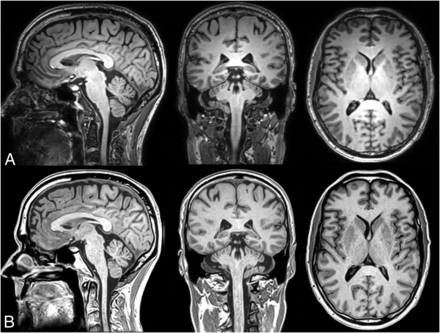

The typical appearance of the conventional and synthetic 3D-T1-weighted images is shown in Fig 1 in sagittal, coronal, and axial reformats. Visual inspection shows a very similar white matter–gray matter contrast, but a somewhat sharper appearance in the synthetic images. Of the 96 data sets uploaded to NeuroQuant, 9 failed to provide segmentation results (9.4%), 5 were based on conventional T1-weighted images (2 at 1.5T and 3 at 3T), and 4 were based on syT1WI (all at 3T). All SyMRI volumes produced a segmentation result.

Representative example of a sagittal, coronal, and axial reformat of the 3D-T1-weighted image stack at 1.2-mm isotropic resolution at a scan time of 6 minutes 10 seconds. The subject is a man, 54 years of age. Upper row (A), conventional T1-weighted NeuroQuant sequence. Lower row (B), synthetic T1-weighted image, created from the R1, R2, and PD maps (SyMRI 22Q2).